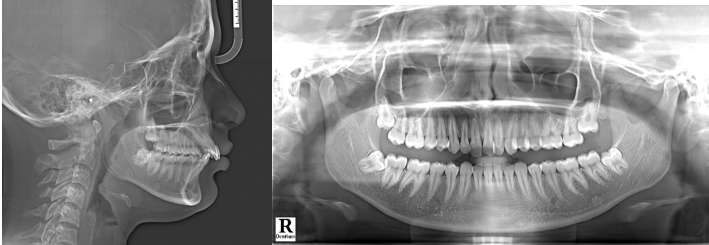

Upon examination, the patient displayed a full-cusp Class II molar relation on right and left sides and an end-on canine relation both side. There was no midline deviation and overjet measured 5 mm. The incisor exposure was increased by 5 mm. The proclination was observed in maxillary incisors while mandibular anterior teeth displayed mild crowding. No abnormality or pathology was observed in temporomandibular joint. (Figure 1).

The detailed analysis of lateral cephalogram disclosed that growth pattern was average (Figure 2) (Go-Gn-SN = 30º). The was maxillary excess in sagittal plane (SNA = 86º), and the mandible was retrognathic (SNB = 77º). The skeletal base was Class II pattern (ANB = 9º and Wits Appraisal = +7mm). Additionally, the analysis indicated proclination of maxillary incisors (Upper Incisor to NA = 31◦) along with relative mandibular incisors proclination (Lower Incisor to NB = 28º). The analysis of models demonstrated a Bolton’s ratio, indicating an excess of 1.8mm tooth material in mandibular anterior and overall mandibular excess (0.2mm).